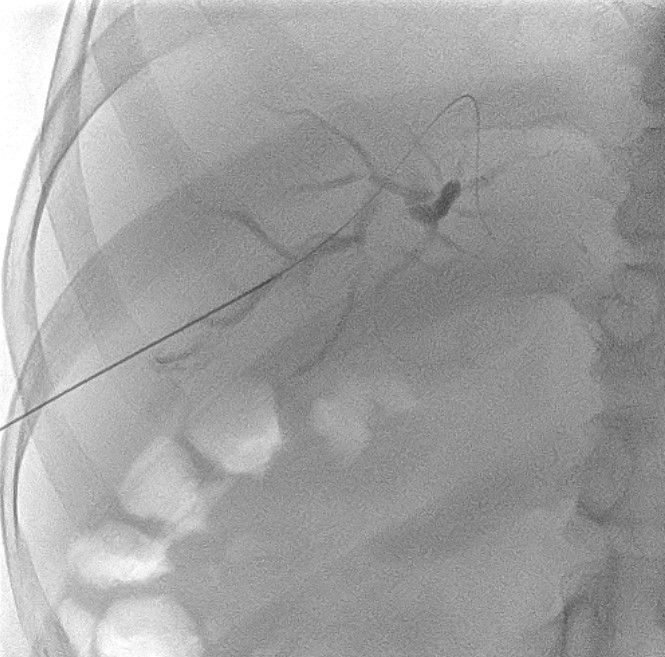

– Successful negotiation of the strictures with a guidewire and catheter.

– Serial dilatation was conducted, opting out of balloon dilatation due to hypervascularity.